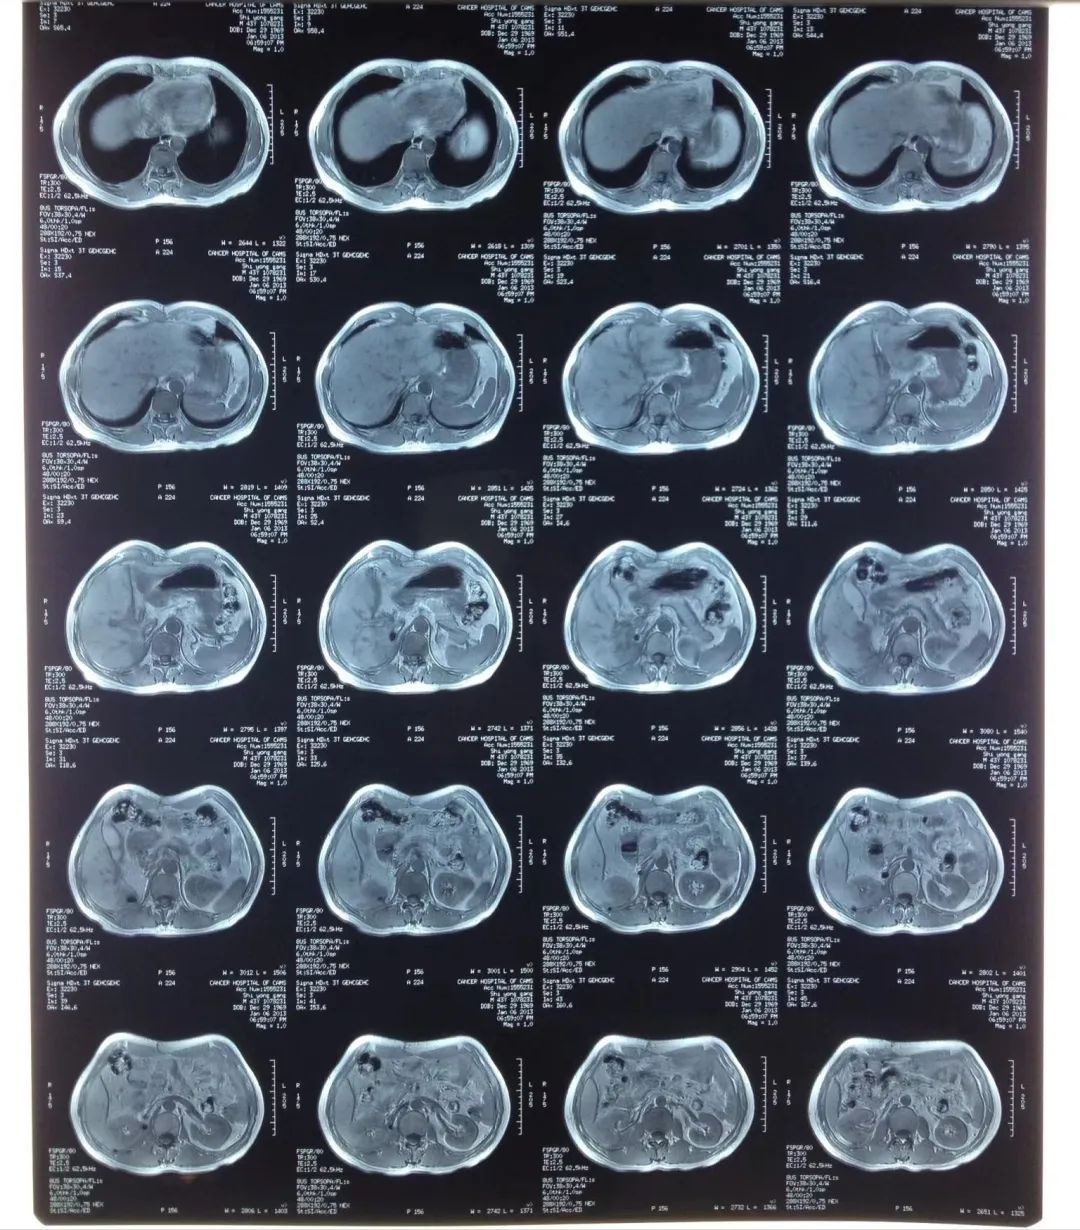

10年间,师永刚共做了60多次增强CT、PETCET、X光。做普通CT累积的辐射剂量,相当于在全球乘坐飞机15000次,而师永刚大部分时候做的是增强CT,辐射剂量是普通CT一倍以上

他去找医生将所有电子病历拷过来,又恢复了十几年前的写作状态。每一张病历,CT片子,处方,都像一把钥匙,帮他穿越回当时的境况。但他觉得好像在写另一个人的故事,当时痛苦的感受似乎被大脑忘记了。